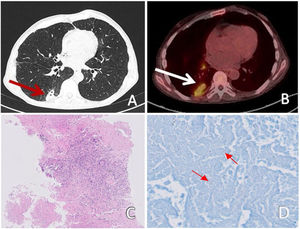

We report a case of a 64-year-old man smoker with occupational exposure to silica dust in mining. He consulted due to persistent dyspnea on exertion and chronic cough. A Computed Tomography (CT) was requested, which described a 37-mm consolidation at the level of the right lower lobe, with pleural contact (Figure 1). This study was completed with 18-fluorodeoxyglucose Positron Emission Tomography (FDG-PET), which found a bilobed consolidation in the periphery of the right lower lobe with spiculated contour and pathological uptake of FDG suspicious of malignancy with a maximum Standardized Uptake Value (SUVmax) of 4.0. Mediastinal and right hilar lymph nodes were suspicious of malignancy too (SUVmax up to 4.3).

(A) Chest CT: consolidation at the level of the right lower lobe with pleural contact (red arrow). (B) PET-CT: bilobed consolidation in the periphery of the right lower lobe (white arrow) and right hilar lymph nodes with pathologic FDG uptake. (C) Pathology: giant cells and necrosis (10×). (D) Microbiology: presence of acid fast bacilli by Ziehl Neelsen stain (little red arrows).

As part of the study, bronchoscopy was performed without endoscopic alterations and an ultrasonic bronchoscopy was accomplished but the samples were insufficient for cytological evaluation. Then a transthoracic lung biopsy was performed with a core needle, observing necrotizing granulomas and Langhans cells. Data was compatible with tuberculosis involvement without appreciating evidence of malignancy.